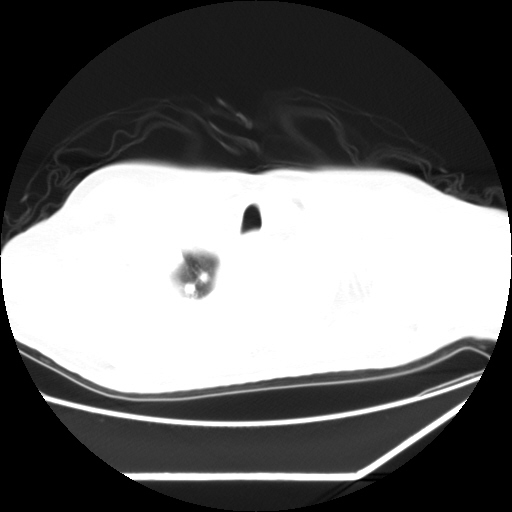

男,57,畏寒,发热

两肺野多发大小不一高密度灶,纵膈内见肿大淋巴结,要考虑转移瘤可能。双侧胸腔少量积液。

双肺多发结节样病灶,部分内见透光区,纵隔内见淋巴结肿大。结核临床如有畏寒,高热,白细胞增高首先考虑迁徙性肺脓肿(多是金黄色葡萄球菌感染)。

注意除外转移瘤。

1)考虑两肺感染性病变(金黄色葡萄球菌肺炎?);建议抗炎治疗后复查排除其他。2)双侧少量胸腔积液。